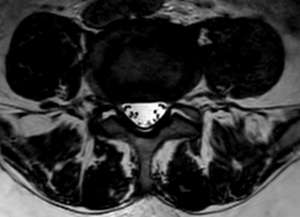

Ernia del Disco Lombare

Cos’è

L’ernia del disco si verifica quando il materiale interno del disco intervertebrale (nucleo polposo) fuoriesce attraverso una fessura dell’anello esterno (anulus fibroso).

Questa fuoriuscita può comprimere le radici nervose, causando:

- Dolore acuto e irradiato lungo la gamba (sciatica)

- Formicolii o intorpidimento

- Debolezza muscolare